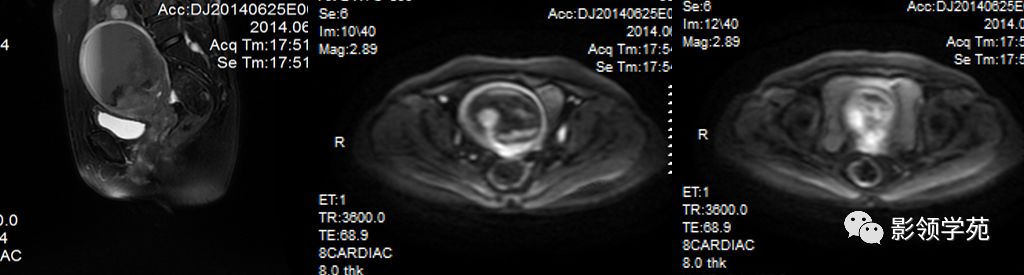

- 扫描序列:SAG T2WI,AXI T1WI+T2WI, COR T2WI 。其中SAG T2WI最重要

MRI多方位成像应用

- Ⅰ期 肿瘤局限于宫颈

- Ⅱ期 肿瘤延伸超过宫颈,但未达盆壁和阴道下1/3( Ⅱ A 无宫旁浸润; Ⅱ B有宫旁浸润)

- Ⅲ期 肿瘤延伸至盆壁和阴道下1/3 ( Ⅲ A 未达骨盆壁; Ⅲ B已达骨盆壁,引起肾积水)

- Ⅳ期 肿瘤延伸超过真盆腔或侵犯膀胱、直肠

宫颈癌MRI表现

宫颈癌可表现为类圆形或不规则形肿块,在T2WI上表现为均匀或欠均匀的高信号,与正常宫颈基质及宫旁脂肪形成良好的自然对比。

MRI

- Ⅰ期肿瘤:侵犯宫颈基质,T2WI等信号肿块,宫颈管扩大及宫颈纤维基质中断

- Ⅱ期肿瘤:宫颈增大,宫旁肿块或宫旁脂肪组织内出现异常信号的粗线状影

- Ⅲ期肿瘤:侵犯至阴道下部,外延至盆壁,或出现肾积水。

- Ⅳ期肿瘤:膀胱壁或直肠壁低信号中断,膀胱壁或直肠壁增厚或腔内肿块。

Ⅰ期

IIA期

IIB期